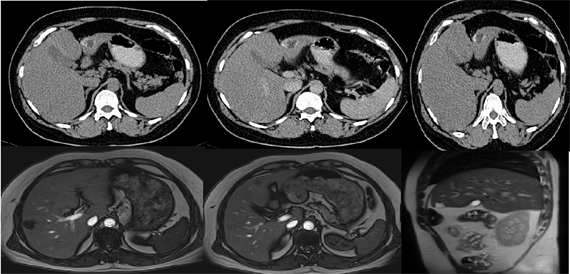

Distribution of LTP and BTTP in both genders and percentages are shown in Table 5. Our results show that overall rate of liver tumor pathologies and biliary tree tumor pathologies are same as found in literature: hemangioma [5] [16] , Figure 1; HCA, Figure 2; FNH, Figure 3; NRH, Figure 4; BC [17] , Figure 5; BCA [15] Figure 6; Cysts, Figure 7; PCLD Figure 8; Hydatid Cysts, Figure 9; HCC, Figure 10; CCA, Figure 11; Lymphoma, Figure 12; metastases, Figure 13.

Figure 10. Imaging of Hepatocellular carcinoma with CT and MR.

Figure 11. Imaging of Cholangiocarcinoma with CT and MR.

Figure 12. Imaging of Limfoma Hepatike with CT and MR.

Figure 13. Imaging of liver metastasis with CT and MR.